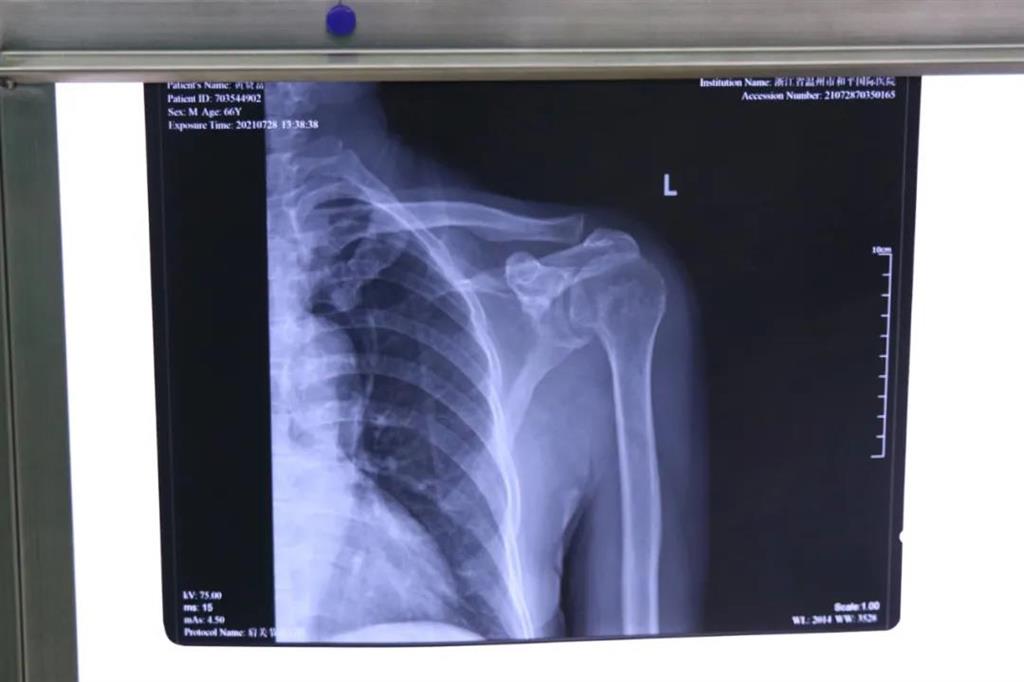

在和平國(guó)際醫(yī)院關(guān)節(jié)鏡微創(chuàng)團(tuán)隊(duì)的協(xié)作下,手術(shù)順利,成功用微創(chuàng)肩關(guān)節(jié)鏡進(jìn)行肩袖修補(bǔ)術(shù)。術(shù)中、術(shù)后患者幾無出血,且手術(shù)切口小,美觀,患者左肩部疼痛得到明顯緩解。